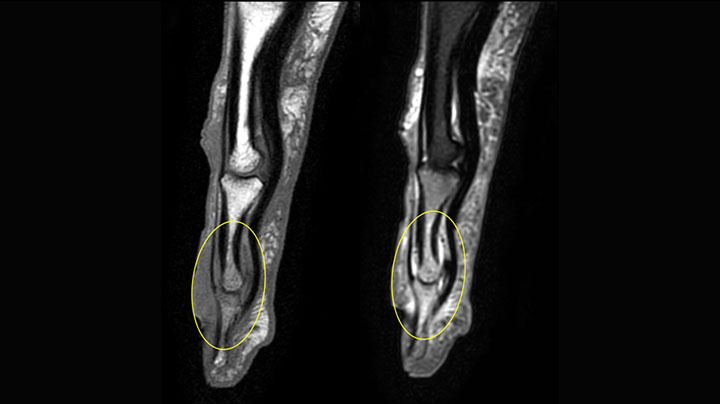

MRI of the finger

MRI of the finger with high SNR and good resolution in a 10 cm field of view on Prodiva 1.5T. The diagnosis in this 63-year-old patient is bone elasmanosis.